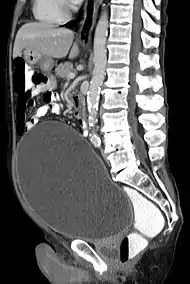

| КТ сечового міхура збільшеного внаслідок ішурії. | |